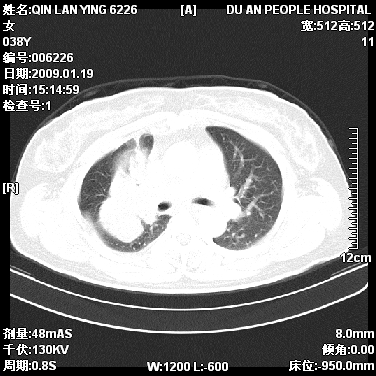

女,38岁,胸疼1个月。wbc:1万4

1)右肺中央型肺癌并右肺上叶阻塞性肺炎、节段性肺不张,纵隔淋巴结转移、右侧胸膜转移、肝脏转移。2)右侧胸腔少量积液。

1、右侧中央型肺癌并阻塞性肺不张,纵隔内、主动脉弓旁、右肺门淋巴结及肝脏转移可能性大,建议纤支镜进一步检查。

2、右侧胸腔积液。

本病例有几个容易诊断的地方:1、右肺上叶前段支气管闭塞,肺不张。2、淋巴结明显肿大。3、肝脏多个类圆形低密度影呈“牛眼征”改变,高度提示转移。

从影像学角度分析      右肺上叶中央型肺癌,并阻塞性不张、肺炎,纵隔淋巴结、膈顶淋巴结转移。

肝内两个大小不等低密度结节,内可见更低密度影,首先考虑肝内转移瘤,但联想到患者wbc1万4,建议楼主还是做个增强比较明确,除外肝脓肿的可能。